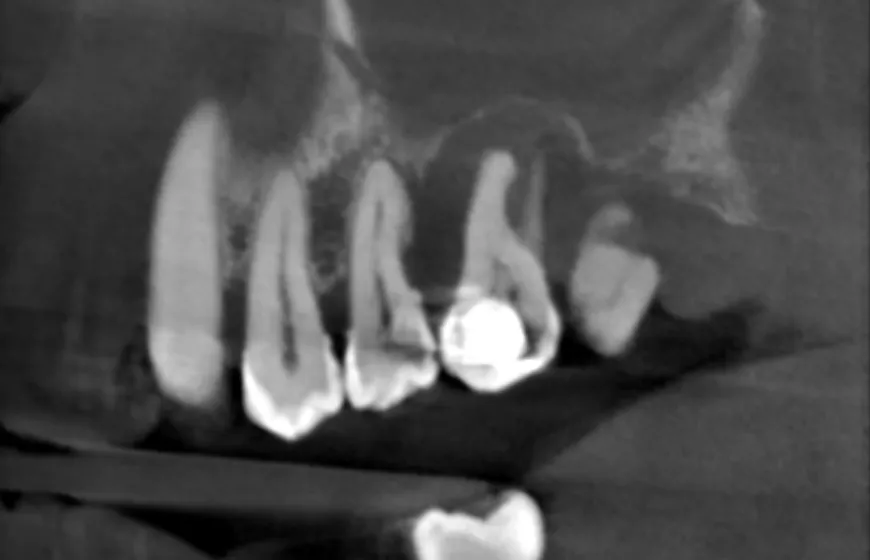

Zdjęcie rentgenowskie zęba jest absolutnie kluczowe w diagnostyce zgorzeli. To właśnie na nim stomatolog może zobaczyć to, co niewidoczne gołym okiem. Na prześwietleniu szukamy charakterystycznych zmian, takich jak:

- Zmiany w okolicy wierzchołka korzenia: Zgorzel często prowadzi do powstania stanu zapalnego tkanek okołowierzchołkowych, co na RTG objawia się jako rozrzedzenie kości (tzw. przejaśnienie okołowierzchołkowe). Może to być ziarniniak lub torbiel.

- Ocena stanu kanałów korzeniowych: Zdjęcie pozwala ocenić liczbę, kształt i przebieg kanałów, co jest niezwykle ważne przy planowaniu leczenia kanałowego.

- Stopień zniszczenia zęba: Widzimy, jak głęboko sięga próchnica i czy ząb jest jeszcze możliwy do uratowania.

Dzięki RTG mogę dokładnie ocenić rozległość infekcji i zaplanować optymalny plan leczenia.